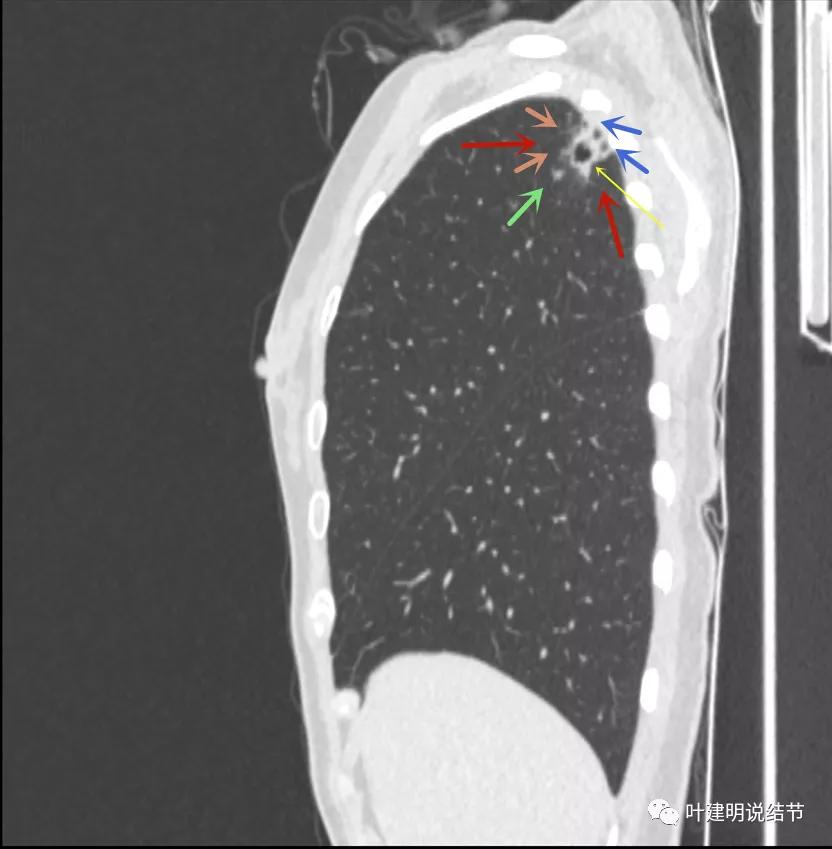

我们再来瞧瞧冠状位与矢状位的图像:

病灶密度高,膨胀性弱,有中间空洞(黄色箭头),囊壁密度过高(粉色箭头);有淡磨玻璃成分(砖色箭头)以及邻近胸膜的明显增厚(蓝色箭头)

有卫星灶,且条索状(绿色箭头),囊壁密度过高(粉色箭头);有空腔征(黄色箭头)

邻近胸膜增厚明显(蓝色箭头),病灶边上部分有淡磨玻璃(砖色箭头)